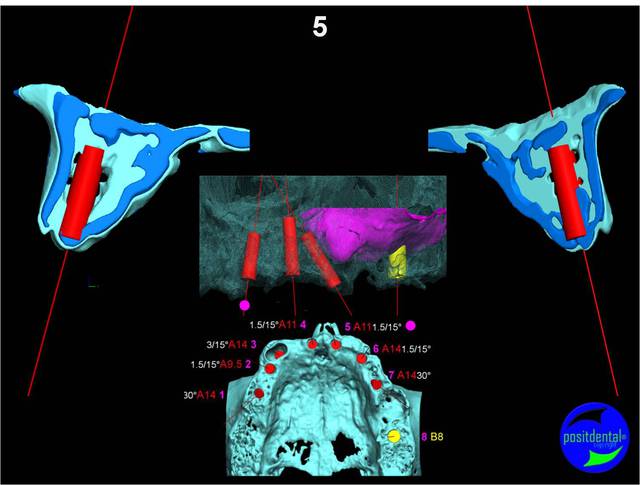

Extraction, pose d’implants Ankylos, pose des piliers Standard définitifs, mise en charge immédiate bi-maxillaire en une chirurgie.

Maxillaire supérieur – extraction 13, 26, 7 implants en MCI, 1 implant en MCR pose summeurs, densification par ostéotme, comblement osseux, bridge provisoire sans fausse gencive avec renfort métallique.

Maxillaire inferieur – extraction 35, 34, 44, 45, 6 implants MCI, comblement osseux, bridge provisoire sans fausse gencive avec renfort métallique.

en attendant la pano voici les coupes de la S.I.A.O.